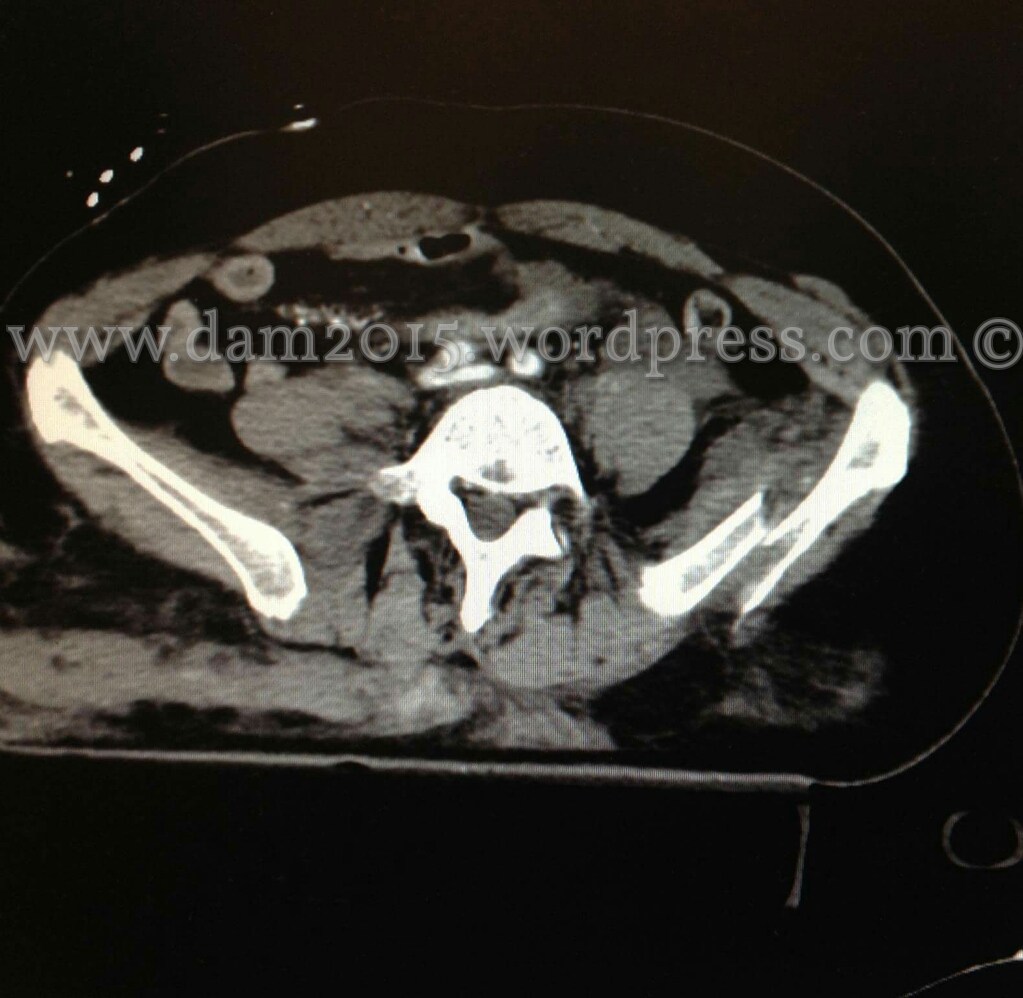

Pz donna, 56 anni.

Incidente stradale.

Shock emorragico in fratture multiple del bacino. Emoperitoneo.

Packing pelvico con estensione in senso xifoideo dell’incisura laparotomica mediana.

Emostasi di lesione mesenteriale e aspirazione di raccolte ematiche nei recessi anatomici.